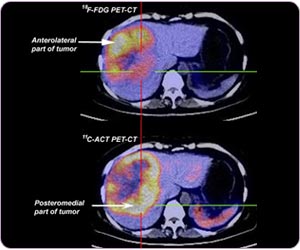

In the same HCC, C-11 ACT and F-18 FDG can be taken up by different parts of the same tumor due to different cellular differentiation